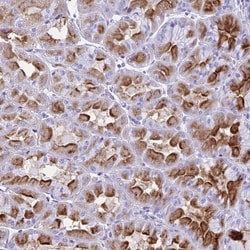

Invitrogen™ ATP4B Polyclonal Antibody

Immunogen sequence: TPDYQDQLRS PGVTLRPDVY GEKGLEIVYN VSDNRTWADL TQTLHAFLAG YSPAAQEDSI NCTSEQYFFQ ESFRAPNHTK FSCKFTADML Highest antigen sequence indentity to the following orthologs: Mouse - 83%, Rat - 80%.

The hydrogen/potassium ATPase, or gastric proton pump, belongs to a family of P-type cation-transporting ATPases. This family of ATPases shares a number of functional and structural similarities including the common feature of consisting of an alpha and beta subunit. Like the ubiquitous sodium/potassium ATPase, the hydrogen/potassium ATPase consists of a large transmembrane catalytic subunit, termed the alpha- subunit which contains sites for ATP binding and phosphorylation, and an associated smaller glycoprotein, termed the beta-subunit which may play a role in maintaining the structural and functional integrity of the complex.

| Immunohistochemistry (Paraffin) | |